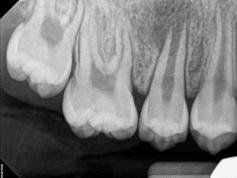

Root Canal Treatment also is known as Endodontics is a branch of dental treatments recognized by the American Dental Association involving treatment of the pulp (root canal) and surrounding tissues of the tooth. When you look at your tooth in the mirror, what you see is the crown. The rest of the tooth, the portion is hidden beneath the gum line, is called the root. Though the outer portion of the root is a hard tissue called dentin, the inside channel or "root canal" contains a pulp of soft tissue, blood vessels, and nerves. Bacteria that are introduced into the pulp as a result of tooth decay, periodontal disease, tooth fracture or other problems, can severely damage the pulp. When that happens, dentists remove the diseased pulp to save the tooth and prevent further infection and inflammation. After successful endodontic treatment, the tooth continues to perform normally.

Every tooth has different numbers of roots and canal systems. With the help of magnification and high tech equipment, Dr. Jung can locate and treat the canals including MB2 on upper molars and MM on lower molars.